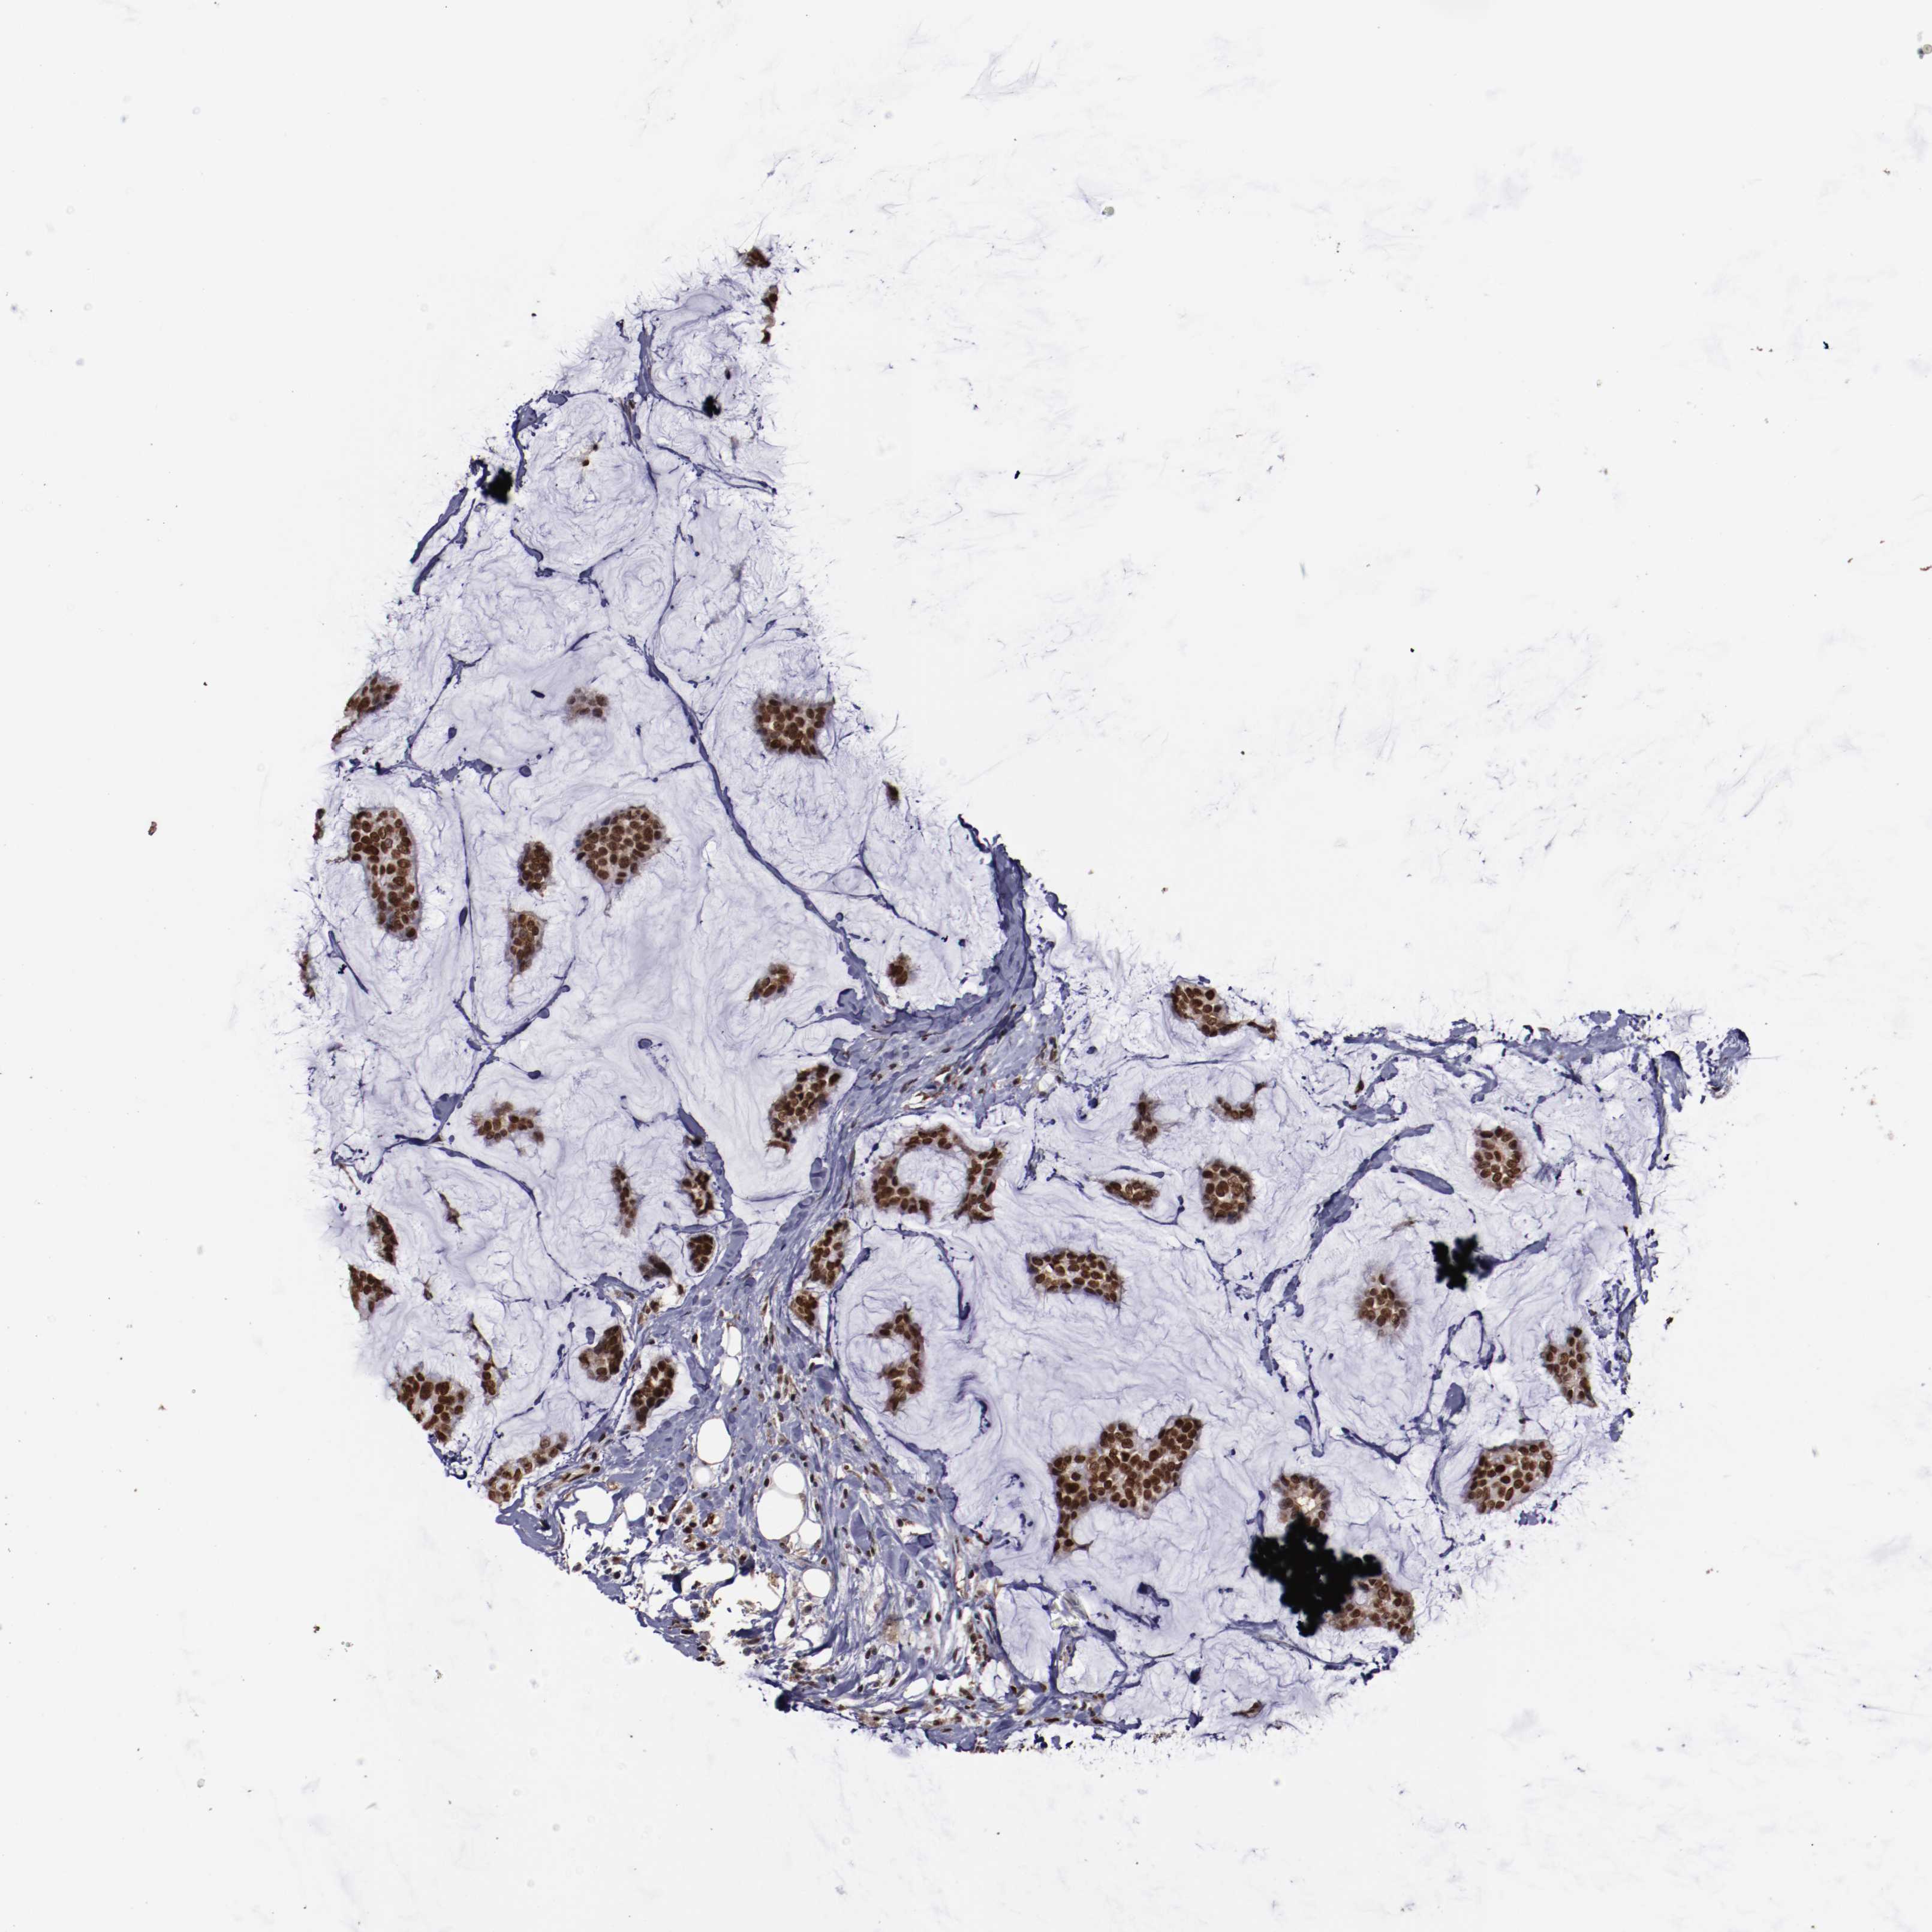

CANCER BREAST CANCER Show tissue menu

BRCA TCGA BRCA VALIDATION PROTEIN EXPRESSION

Breast cancer

Human cancer

Breast invasive carcinoma